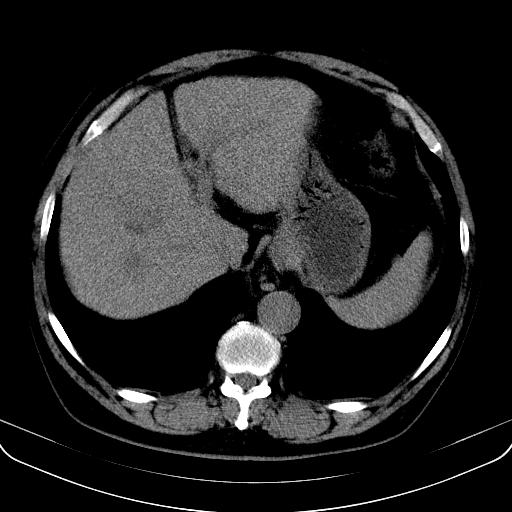

以下是引用jia119在2008-3-5 13:31:00的发言:[br]肝内多发片状低密度影,密度不均,我还是考虑肝ca可能,另肝内小囊肿,胆囊增大。

以下是引用形影不离在2008-3-5 12:18:00的发言:[br]肝硬化伴门脉高压征,肝内占位待排,增强再说.

以下是引用随光逐影在2008-3-5 21:11:00的发言:[br]肝硬化伴门脉高压(食管下段静脉曲张),肝癌不排除。建议:行ct增强扫描检查。

以下是引用同在2008-3-5 13:56:00的发言:[br]考虑肝癌可能性大,胆囊增大.